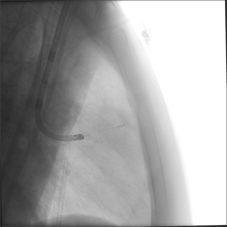

超声定位图(左)CBCT的定位图(右)

术中CBCT确认冷冻消融完全覆盖病灶

术中第一次冷冻情况(左)和术中第二次冷冻情况(右)